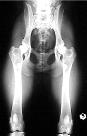

FONDAZIONE SALUTE ANIMALE

CONTROLLO DELLADISPLASIA DELL’ANCAE DELGOMITO DELCANE

ATTIVATA LA NUOVA CENTRALE

UFFICIALE DI LETTURA

RICONOSCIUTAALIVELLO NAZIONALE ED EUROPEO

zione professionale. Un ulteriore importante chiarimento dovrà riguardare i rapporti tra gli Ordini e le Associazioni che rappresentano i professionisti non iscritti agli Albi.

La Centrale di Lettura FSA é aperta a tutti i medici veterinari:partecipa anche tu al controllo della displasia dell’anca e del gomito del cane!

Cogli l’opportunità per:

incrementare i servizi offerti alla tua clientela

qualificare il tuo impegno nella prevenzione delle malattie ereditarie del cane

esaltare il tuo ruolo di consulente qualificato per allevatori e cinofili

Per conoscere le modalità di adesione puoi:

• telefonare alla FSA0372403511

• visitare il sito internet della FSA: www.fsa-vet.org

• telefonare al numero verde Bayer 800-015121